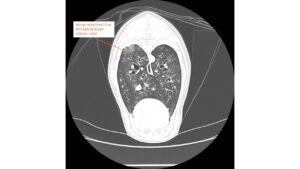

“We performed a bronchoscopy (a thin tube with a tiny video camera being sent down the throat into the lungs) to evaluate his airways and what was found is not for the faint-hearted. It revealed hundreds of worms within the dog’s airways.

“The worm was identified as Crenosoma Vulpis, which is also known as the fox lungworm, so it’s likely that our patient got infected either by eating a snail or a slug, which host the parasites, or by swallowing the larvae themselves when eating grass.”